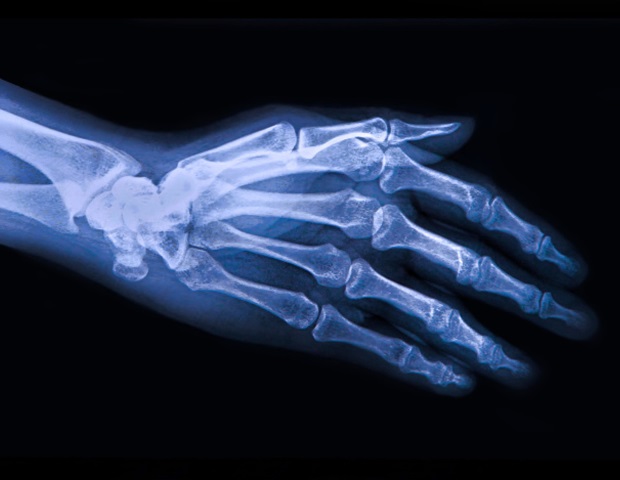

La croissance normale et régulée des os du squelette est un élément crucial de la croissance des mammifères. Il s’agit d’un processus complexe impliquant la croissance de cellules cartilagineuses ou chondrocytes, leur transformation en cellules de construction osseuse ou ostéoblastes et la formation de nouveaux vaisseaux sanguins pour alimenter le tissu osseux nouvellement formé.

Alors que les ostéoblastes évoluent à partir d’une variété de cellules progénitrices, plus de 60 % des ostéoblastes chez les mammifères proviennent d’une classe appelée chondrocytes hypertrophiques (HC). Les HC sont des cellules polyvalentes impliquées dans diverses tâches de croissance et de maintien des os, notamment la cicatrisation des blessures et la formation normale des vaisseaux sanguins. Cependant, les mécanismes spécifiques qui sous-tendent la manière dont les centres de santé exécutent ces tâches ne sont pas connus.

Après avoir étudié précédemment comment les HC peuvent se transformer en tissu osseux, l’équipe a examiné les nouvelles formes que prennent les HC à différents stades de la croissance osseuse. Tout d’abord, l’équipe a créé des souris transgéniques avec suppression sélective des HC. Comparées aux souris normales, ces souris ayant subi une ablation HC étaient plus petites, avec des membres plus courts, un crâne arrondi et une colonne vertébrale mal formée. Leurs os longs, comme le fémur, avaient moins de vaisseaux sanguins.

(HC-ablation) les souris ont montré un phénotype de nanisme, une structure osseuse trabéculaire altérée et une guérison prolongée des blessures causées par les trous de forage, soulignant le rôle essentiel de l’extension de la lignée HC dans le développement et la réparation des os.